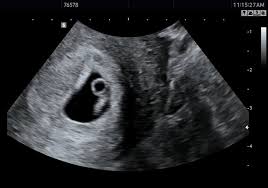

▶ 초음파에서 태아가 눈에 띄게 보이기 시작하는 시점은 보통 임신 6~7주차입니다.

하지만 개인마다 배란일이나 착상 시점 차이로 ±1주 정도 차이가 날 수 있어요. 그래서 생리 예정일이 지나고 2주 후쯤 산부인과를 방문하면 정확하게 확인할 수 있어요.

▶ 임신이 시작되었는지 빨리 확인하고 싶다면 임신4~5주차에 확인하세요. 임신낭이 보이는데 태아 자체보다는 임신이 시작되었음을 나타내는 첫 신호입니다.